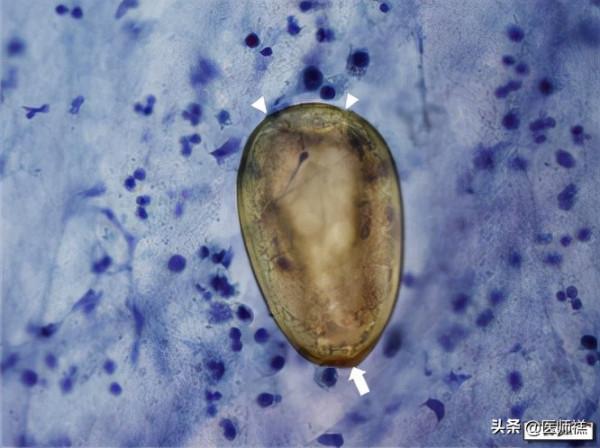

但是禚醫生想告訴你,我們都錯了,上述這些表現雖然其他疾病也會出現類似的表現,但是在這些患者糞內和咳出的痰液中都發現了一個呈現卵圓形呈現出金棕色的蟲卵,並且這些病例他們都有一個共同的特徵,那就是吃了醉蟹!!!更準確地說是吃了溪螃蟹!

肺部組織穿刺發現的蟲卵(蟲體發育成熟後在肺部產卵,卵發育成童蟲後繼而在全身繼續遊走)